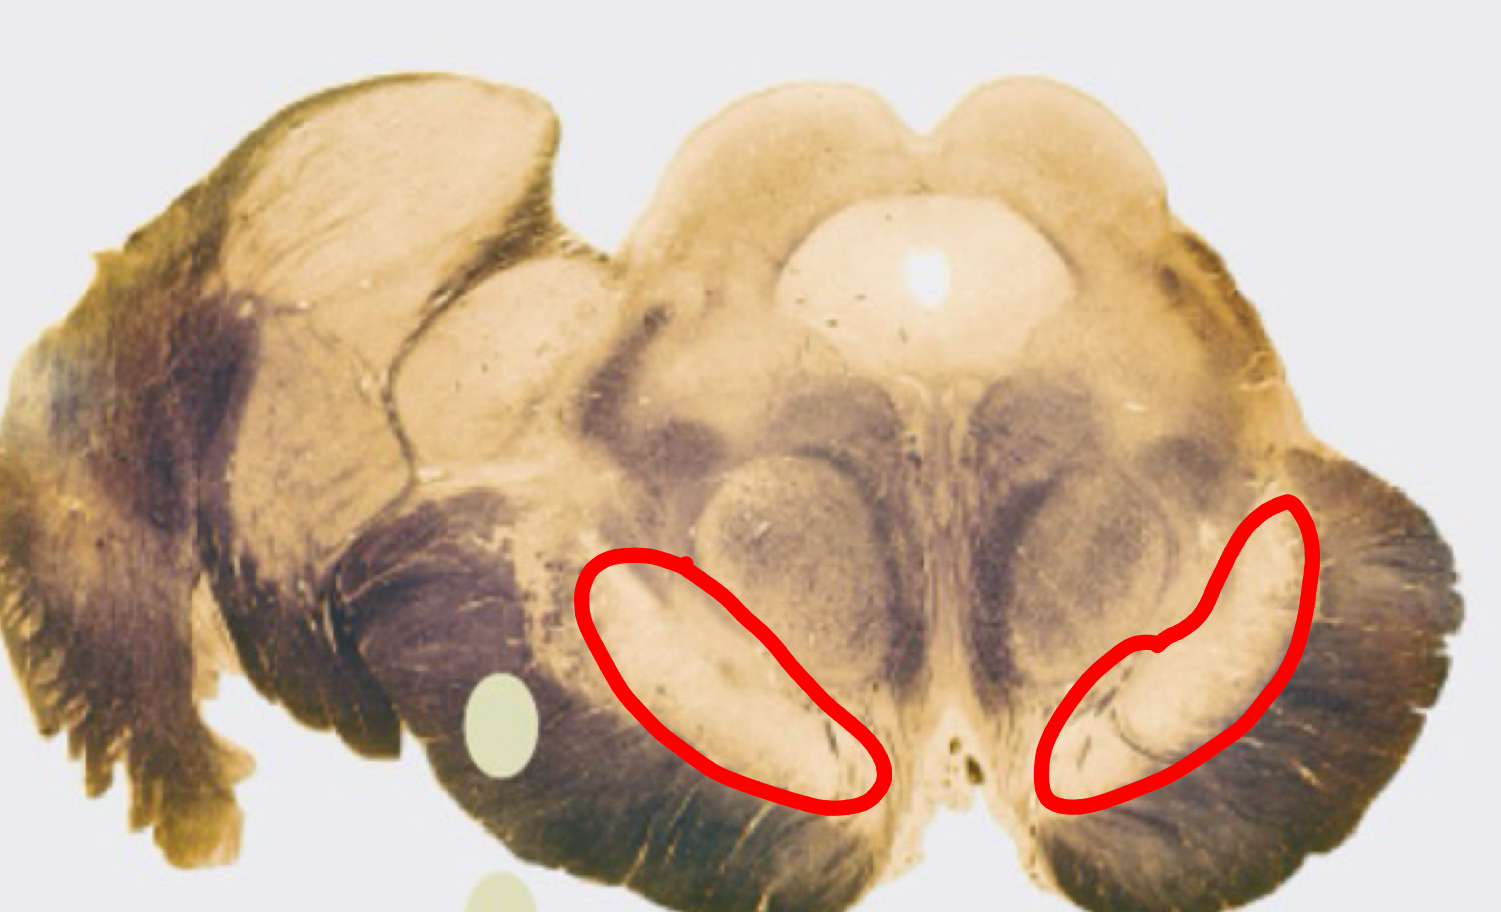

hippocampus with fimbria

Fimbrae

crus of fornix